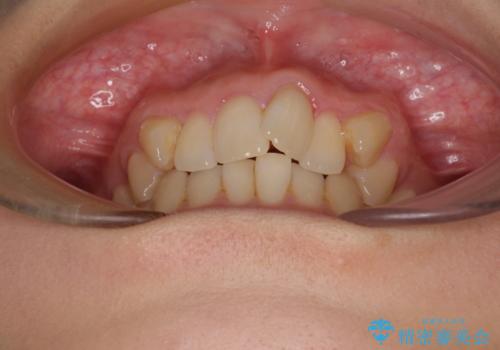

- 目立つ八重歯を気にして来院された患者様です。

下顎歯列の叢生は軽度であることと、口元の突出感が全くなかったことから、八重歯解消のために上顎左右第一小臼歯を抜歯し、ワイヤー装置にて矯正治療を行うこととしました。